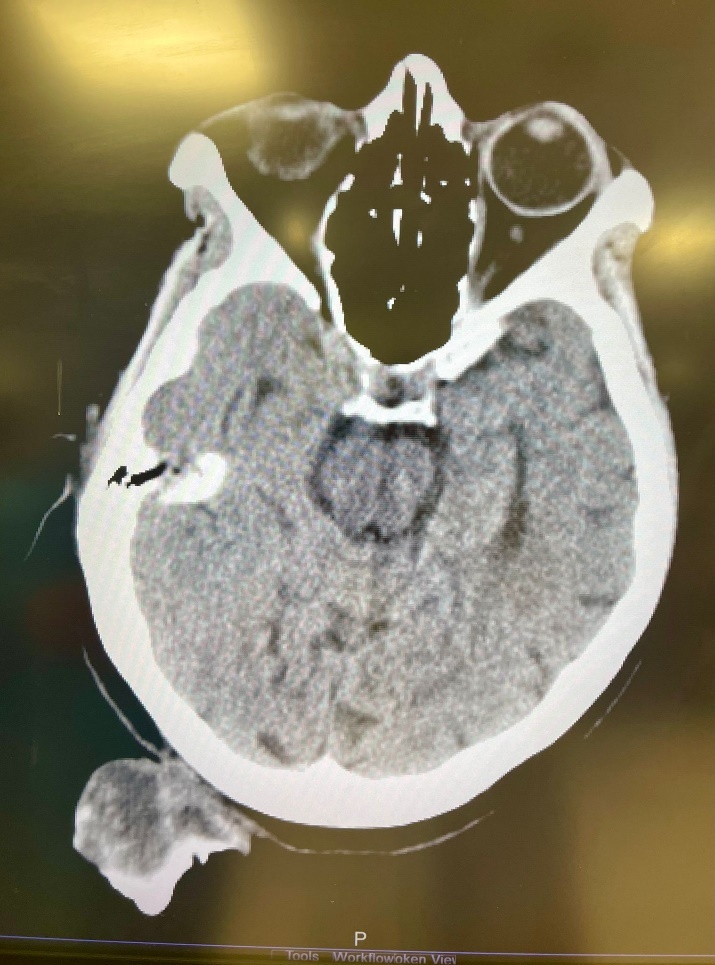

A 75-year-old woman presented to Al Ahli Hospital’s surgery clinic with a painless lesion on the back of her head that had been growing for years. The lesion has grown faster lately, annoying her while lying down and sleeping. The patient is a non-smoker. She had a history of recurrent stasis ulcers on both legs. She had no known drug allergy. Her family history did not include any relevant genetic information or psychosocial history. The physical examination showed a big coiled horn in her occipital area, which measured about 25 centimetres (Fig.1). A Computed tomography (CT) scan revealed a large soft tissue mass arising in the occipital area to the right of the midline with calcification but no bony attachments. The base of the horn is shorter than its length (Fig.2).